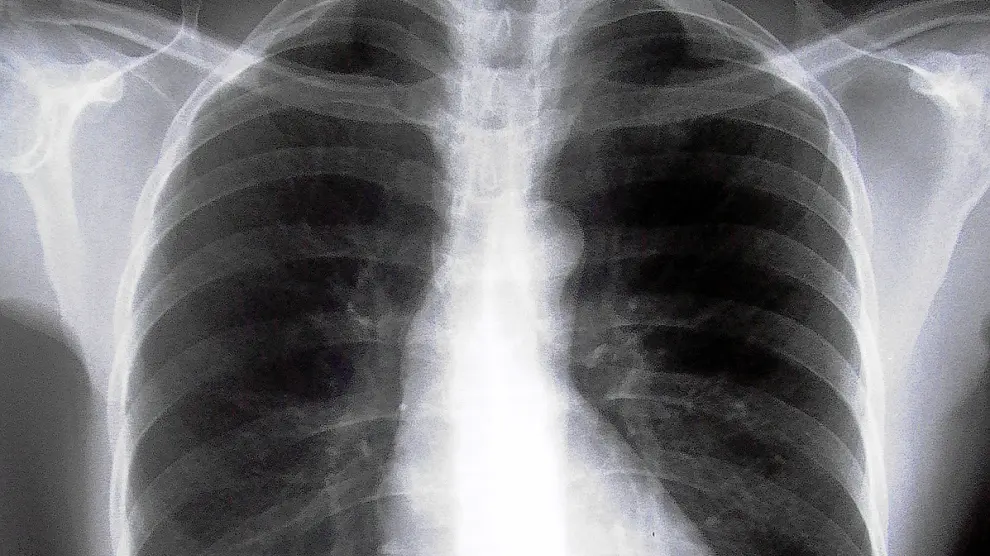

El enfisema es un trastorno en el que los alvéolos se inflan de manera excesiva, lo que produce una disminución de la función respiratoria.

Está asociado principalmente al tabaquismo continuado y es una manifestación de la enfermedad pulmonar obstructiva crónica (EPOC), ha señalado el doctor Flandes.

El doctor Flandes ha indicado que el enfisema pulmonar grave provoca que el pulmón sea menos elástico, por lo que el tejido queda distendido, empujando el diafragma hacia abajo e impidiendo que el paciente pueda respirar correctamente.